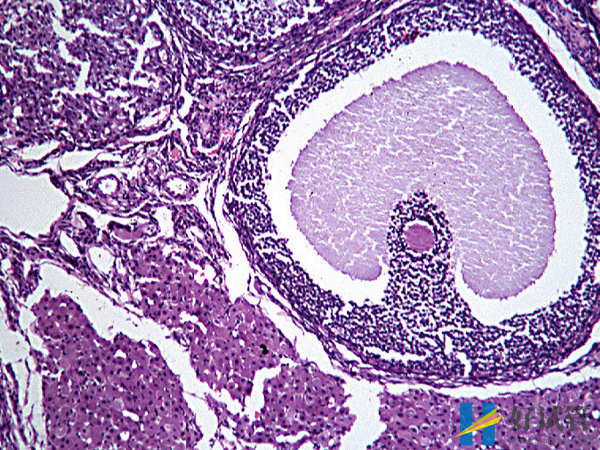

优势卵泡能维持几天

当优势卵泡发育成熟后,从卵巢中排出会在体内存活48小时左右,也就是两天。所以在这两天的时间里面就可以同房,这样是可以提高受孕的几率。在这48个小时之内,前二十四个小时的受精能力是最强的,后二十四个小时的受精能力就会有所下降直到死亡。而进行同房前男方也需要禁欲,这样才能提高精子的质量,进而增加受精几率。

无论是正常备孕还是做试管婴儿,当监测到优势卵泡的时候,并非就一定能够怀孕,优势卵泡只是说明卵泡会大概率成熟并排出,而能否怀孕则和多方面因素有关,主要就有:

1.子宫内膜因素:当精子和卵子结合形成受精卵后,能不能成功着床,就需要看内膜的厚度是不是在标准范围内,如果内膜的厚度在8-12mm之间,则是最适合着床的。如果内膜偏厚或偏薄,那么就不利于着床;

2.精卵质量:需要注意的是,优势卵泡是质量好不好以及精子质量好不好,就决定着能否成功的受精并着床,如果卵子质量或精子质量不佳,都会影响到受精;